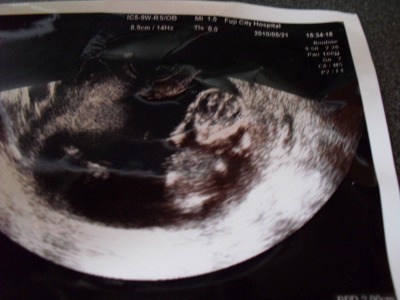

今日は内診とまた別にお腹の上からのエコーで私も一緒に双子を見ることが出来ました。

お医者さんが「心臓動いてますよ^^」と見せてくれるのですが、ぐじゃぐじゃしててよく分かりませんでした^^;

二人いっぺんに映すのが結構難しいみたい。

頭が二個並んだところが見えました^^;

なんだか病院がバタバタしていて写真をくれなかったもので後で看護師さんに尋ねると、お医者さんがもうどっか行ってしまったらしく一枚なんとか残ってるのをくれました。

看護師さんが「頭二つね^^」とくださったのですが、なんかムンクの叫びみたいな写真でしたw